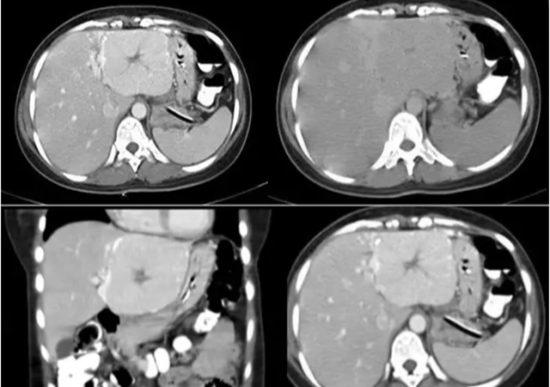

比较常见的肝脏的良性肿瘤,发病率也比肝囊肿高,且女性发病率约是男性的五倍左右,形成原因也和发育有一定的关系,典型血管瘤在增强CT上会有由边缘向中央渐进性强化的表现。肝血管瘤一般生长缓慢,体积较小,小于5cm的肝血管瘤,基本无不适症状,定期体检即可。当血管瘤体积超过5cm,此时可在腹部触及包块,如伴有恶心、呕吐、腹胀等不适症状,或者压迫到周围的肝外胆道、肾脏、十二指肠、门静脉系统时,就需要干预治疗了。

IMG_262